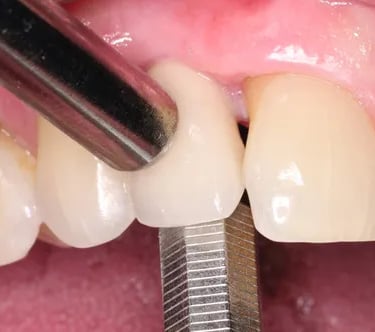

Movilidad del implante

La movilidad del implante es un signo de que el implante no se ha integrado correctamente con el hueso.

Los pacientes notan que el implante se mueve al morder o tocarlo.

El tratamiento incluye la evaluación y, en muchos casos, la extracción del implante móvil y la preparación para uno nuevo.